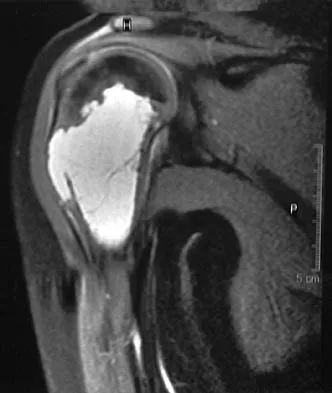

A 28-year-old man has a painful nodule on the plantar aspect of his foot in the midarch. Use of a soft orthosis has failed to provide relief. Examination reveals that the mass is approximately 2 1/2 cm in diameter, firm, and tender to palpation. An MRI scan confirms the presence of a plantar fibroma. Management should now consist of